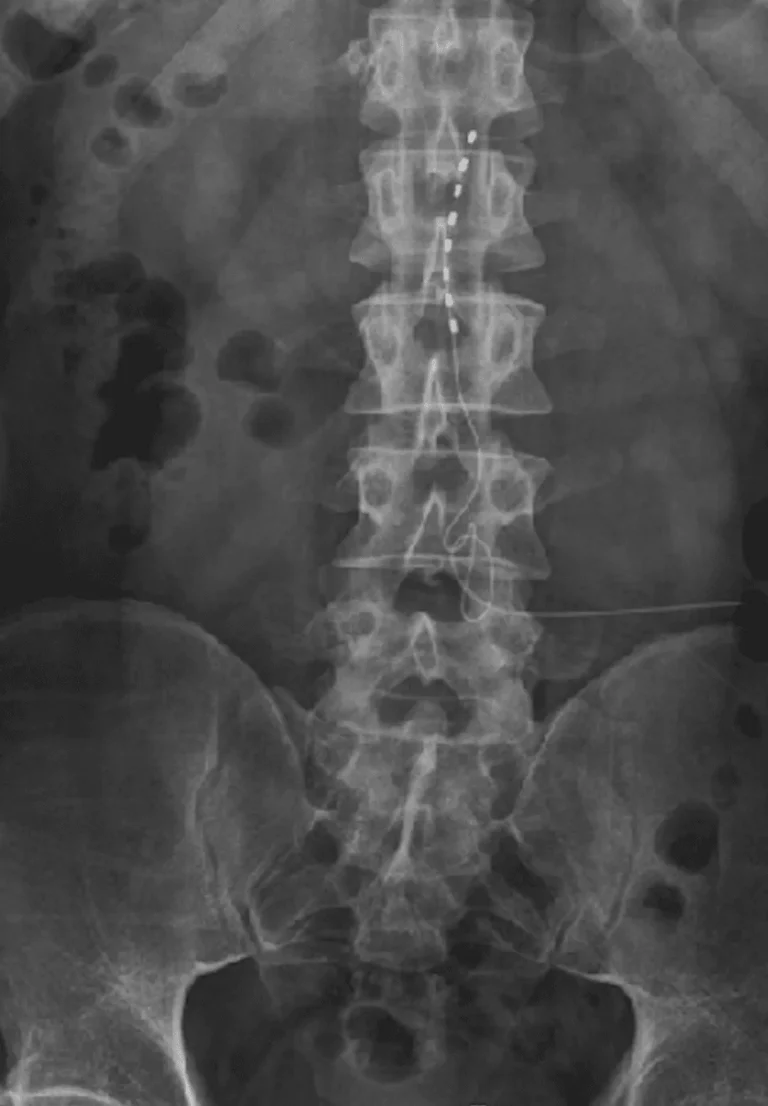

X-ray image showing a spinal column with a spinal cord stimulator implant.

Lead Migration

Implanted leads shift from their original position, causing loss of pain relief and requiring revision surgery.